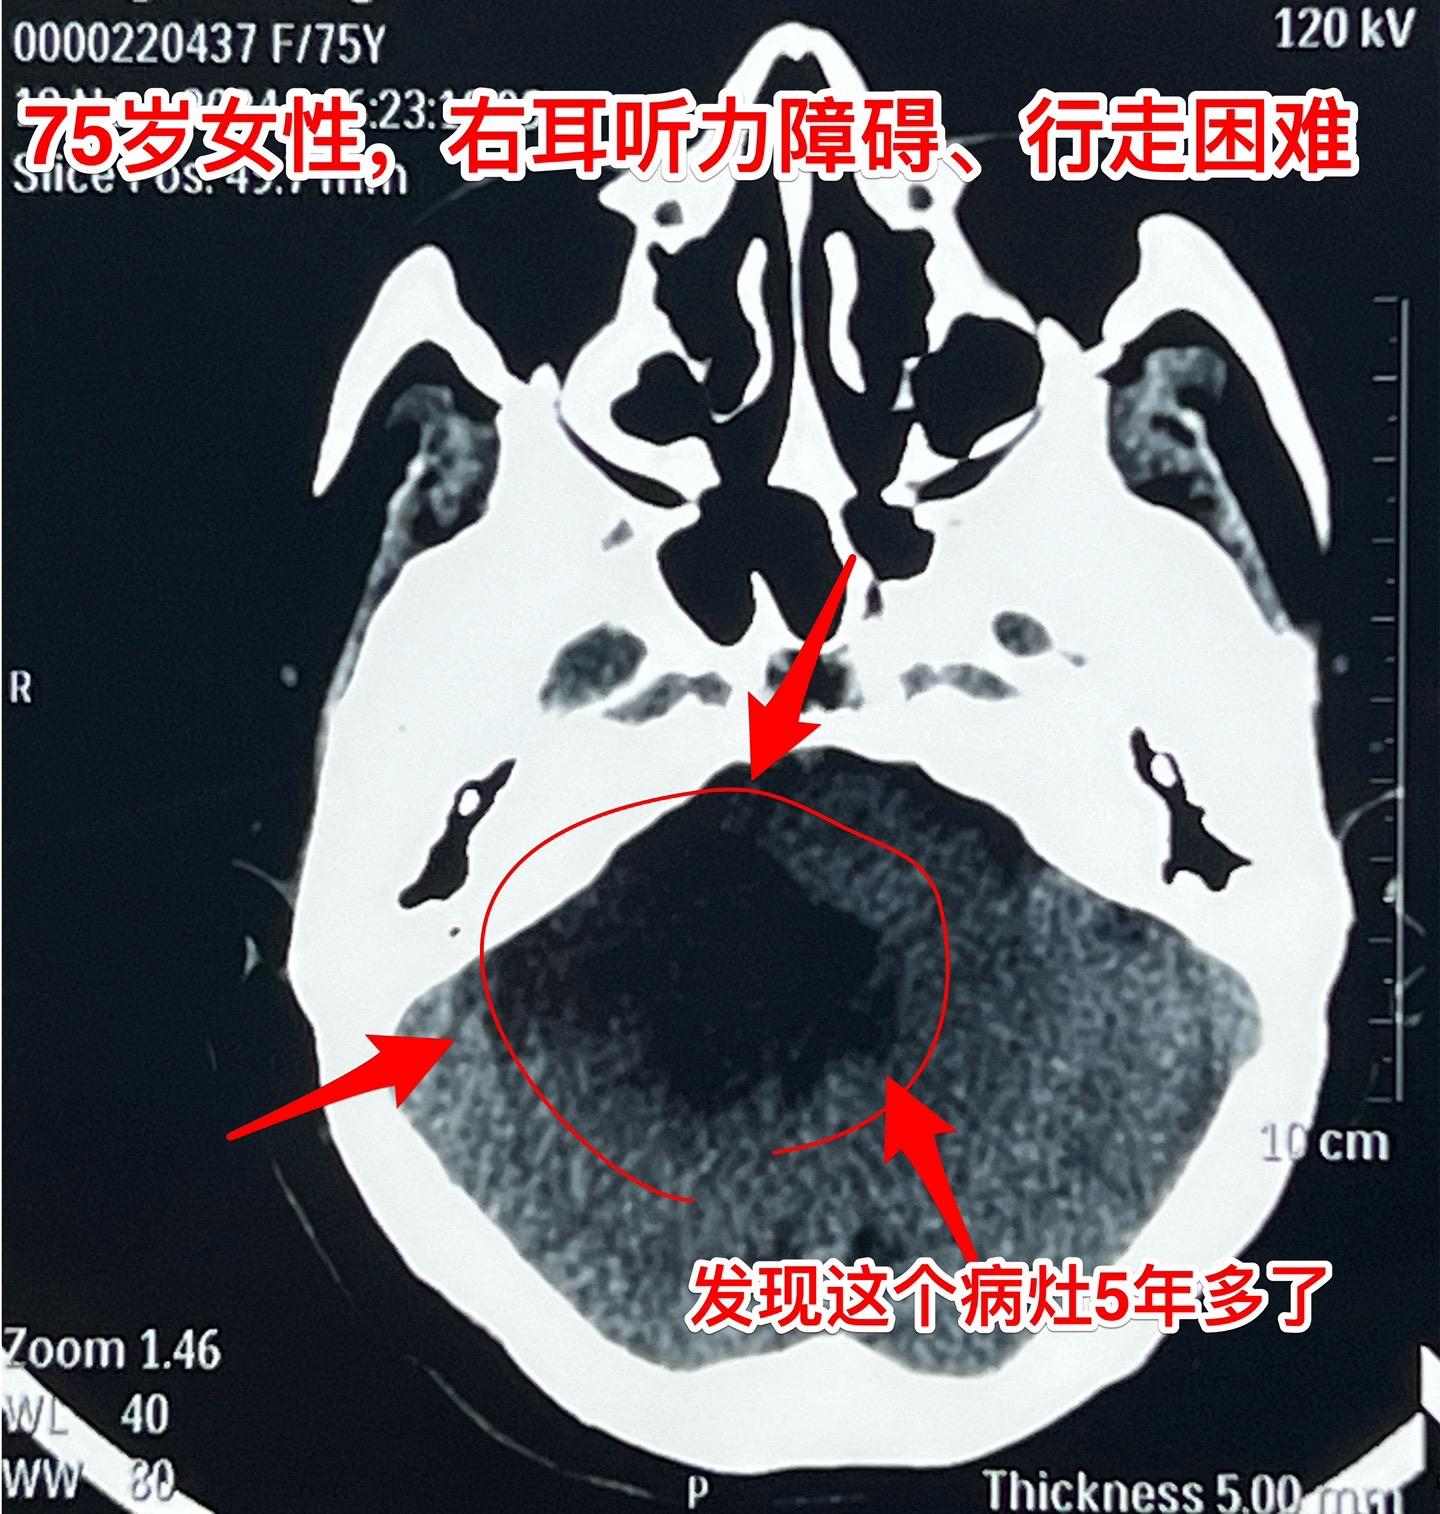

75岁的老奶奶决定接受开颅手术了!75岁的辽宁省海城老奶奶在5年前就曾发现脑部长了一个可疑肿瘤(怀疑为表皮样囊肿或者胆脂瘤),右耳听力下降。当时在沈阳就医,医生建议作手术,但是考虑到病人已经70岁高龄了,手术风险很大,当时老人和家属就决定不作手术。 在五年时间内老人的病情在慢慢加重,逐渐出现行走困难,生活质量越来越差。儿女孝顺,都想方设法地希望能够改善老人的生活质量! 老人的女婿有个表哥,张先生,患颅咽管瘤,曾经在2016年因颅咽管瘤复发了在我这里作了手术。手术后8年了,